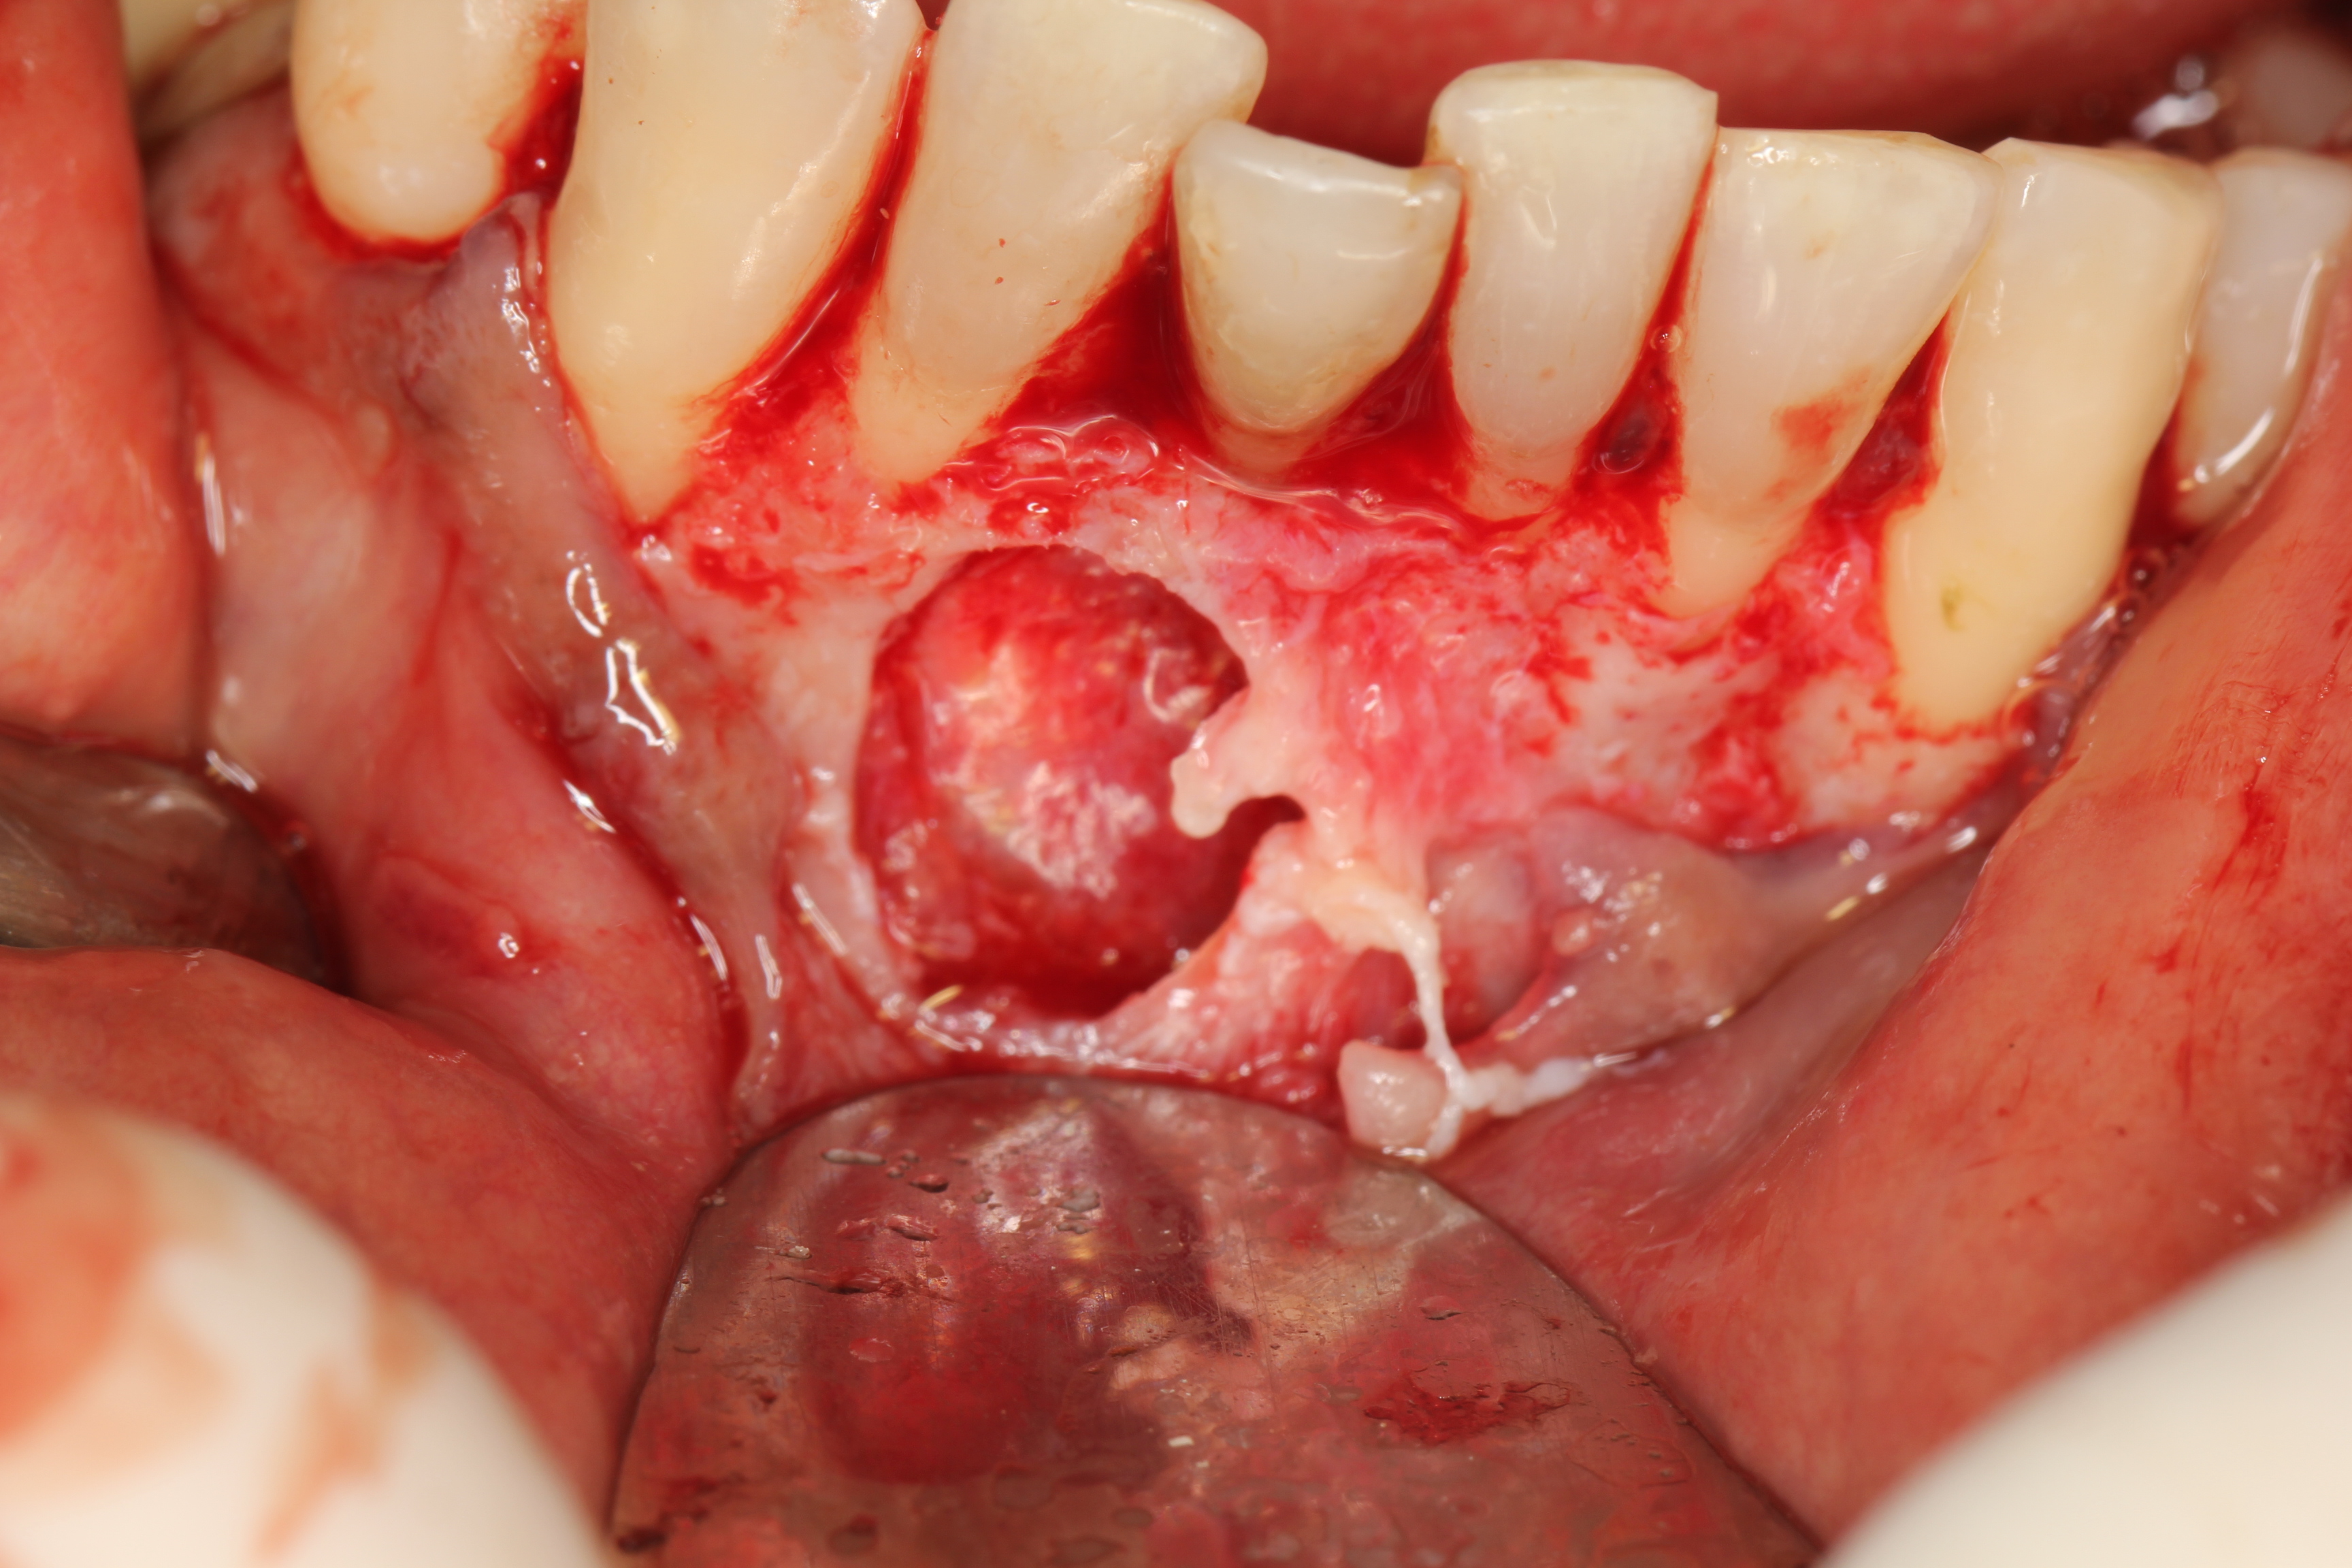

O objetivo deste estudo foi descrever uma técnica de tratamento conservadora, cuja conduta preconizada foi a realização da descompressão seguida pela enucleação cística através do relato de um caso de cisto periapical de grande extensão. Paciente de 50 anos de idade, melanoderma, apresentando cisto periapical com aproximadamente 4,5 cm em seu maior diâmetro associado ao incisivo central inferior esquerdo. Na primeira etapa do tratamento foi realizada descompressão cística e biopsia incisional, cujo exame histopatológico confirmou o diagnóstico clínico. Após 25 semanas de acompanhamento, houve uma considerável regressão do tamanho da lesão e a mesma foi enucleada sem comprometimento dos elementos dentários envolvidos e dos tecidos adjacentes. O relato de caso evidenciou que o tratamento cirúrgico e conservador pode ser um recurso em cistos periapicais de maior dimensão, sendo importante a cooperação do paciente no acompanhamento pós-operatório.